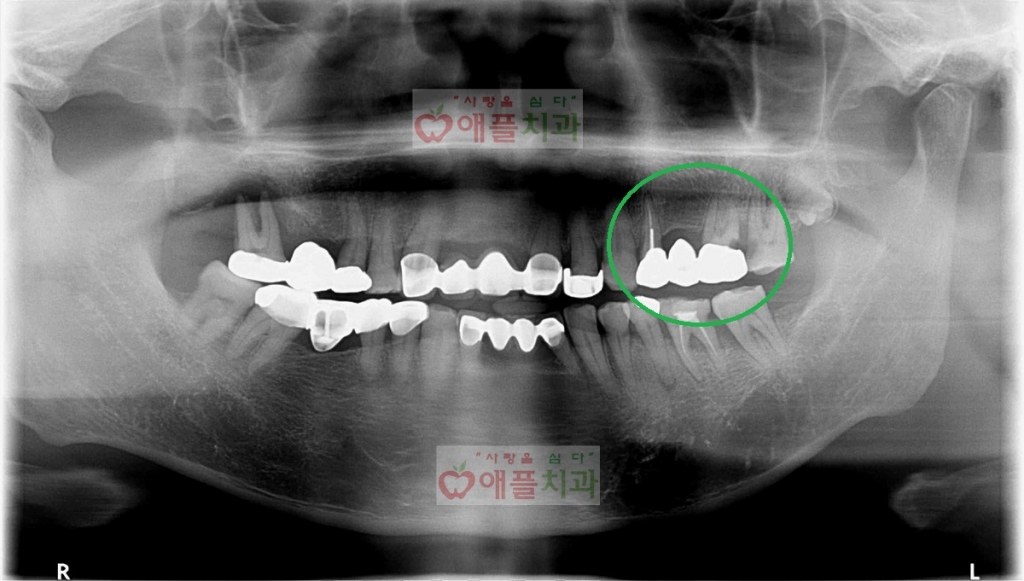

50대 여성 환자분께서 어금니가 장기간 결손되어 병원에 오셔서 중대결심을 하셨고 치아뿌리만 남아있는 신경관이 감염되어 잇몸에 고름이 차있었습니다(화살표). , 디지털 임플란트를 사용하기로 결정하고 상하로 나누어 수술을 진행합니다. 컴퓨터 프로그램으로 발치 후 가상 치아를 식립하는 상악 컴퓨터 모의 수술 사진입니다. 임플란트는 계획된 보철 위치에 따라 가상으로 배치됩니다. 마지막으로 계획된 위치에 임플란트를 배치하는 데 도움이 되는 수술 가이드를 설계합니다. 병원에서 디자인한 파일을 3D프린터로 출력하면 수술이 가능하다. 보형물은 컴퓨터 시뮬레이션을 통해 매우 곧고 가늘고 수술 시간이 길지 않았으며 여러 개의 보형물을 식립했음에도 불구하고 눈에 띄는 부종이나 통증이 없었습니다. 내가 해냈어. 임플란트의 방향이 정확하기 때문에 보철물은 좋은 형태로만 들어갈 수 있습니다. 시술 전후 사진입니다. 중간중간 잇몸치료를 진행하면서 치석도 함께 제거되는 것을 관찰할 수 있었습니다. 대전디지털임플란트전문의원입니다. 감사해요.대전광역시 중구 대종로 626 클린디치과 3층